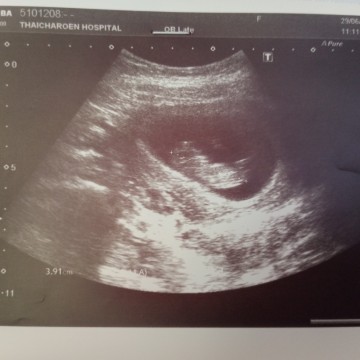

10weekจ้า